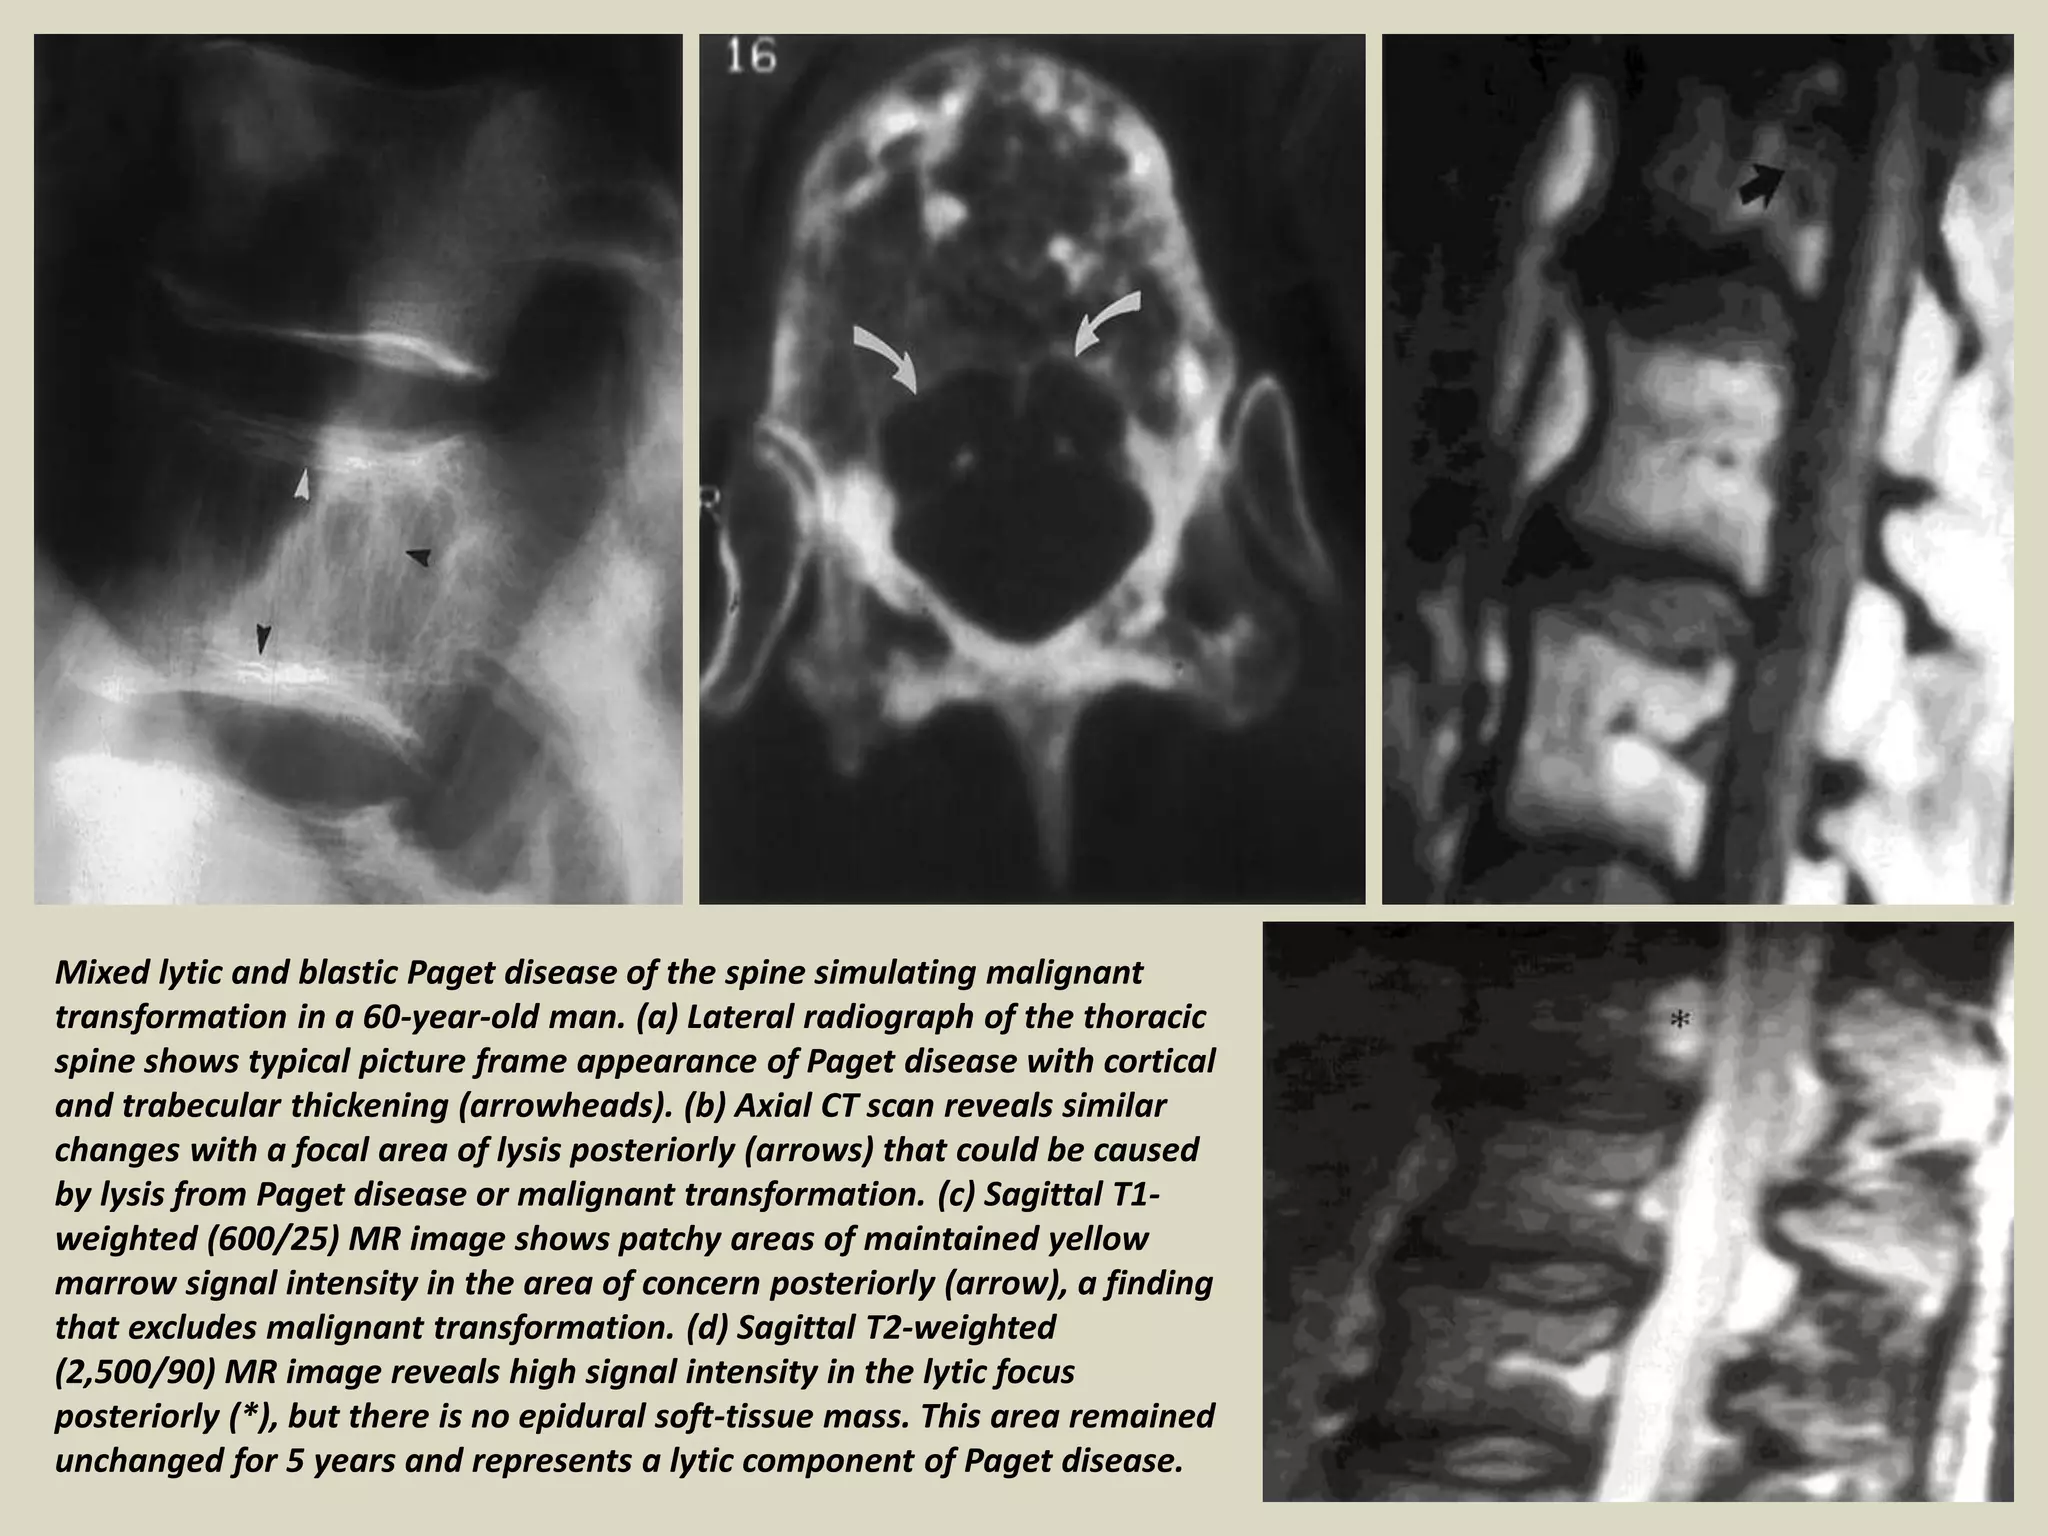

Mixed lytic and blastic Paget disease of the spine simulating malignant

transformation in a 60-year-old man. (a) Lateral radiograph of the thoracic

spine shows typical picture frame appearance of Paget disease with cortical

and trabecular thickening (arrowheads). (b) Axial CT scan reveals similar

changes with a focal area of lysis posteriorly (arrows) that could be caused

by lysis from Paget disease or malignant transformation. (c) Sagittal T1-

weighted (600/25) MR image shows patchy areas of maintained yellow

marrow signal intensity in the area of concern posteriorly (arrow), a finding

that excludes malignant transformation. (d) Sagittal T2-weighted

(2,500/90) MR image reveals high signal intensity in the lytic focus

posteriorly (*), but there is no epidural soft-tissue mass. This area remained

unchanged for 5 years and represents a lytic component of Paget disease.